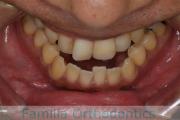

No.22V-029

- 叢生

- 上顎前突

- 19歳

- 男性

- 8448

- FEA 022

- 92万円

でこぼこを治したいということで来院されました。上下左右から親知らずも第一小臼歯も抜歯が必要で、歯科矯正アンカースクリューを併用して大臼歯を後ろに引っ張りながらの治療でした。3年弱、35回程度の通院が必要でした。

叢生が著しく、後戻りのリスクがあります。またアンカースクリューが必須のため、もしもスクリューが安定しないと、治療が難しく長くなってしまう恐れがありましたが、幸い脱落は見られませんでした。